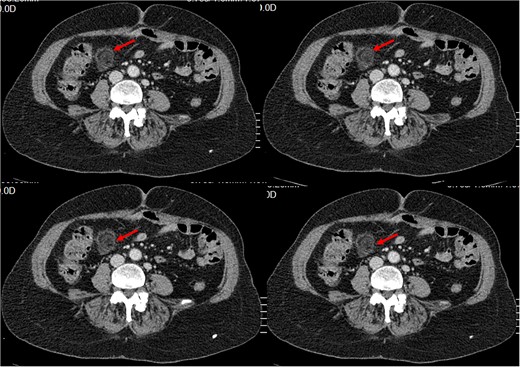

History of Present Illness: The patient reported a sudden onset of sharp pain in the right lower quadrant of the abdomen with no other symptoms. Physical examination revealed tenderness in the same area. Blood work showed an elevated white blood cell count of 13.10 × 1000/𝜇l (4, 8–10) with neutrophilia (87.3%). And C- reactive protein at 45. A CT scan was performed, which showed a typical ‘dot sign’ (Fig. 1), confirming the diagnosis of EA.

Small intra-peritoneal ovoid fatty mass, well limited by a thin border «Ring Sign/ central dot sign», enhanced after contrast, surrounded by inflammatory changes.

Outcome: The patient’s pain disappeared and tenderness in the right lower quadrant resolved. Follow-up imaging showed resolution of the ‘dot sign’.